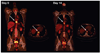

Figure 1

Intrapatient heterogeneity in the expression of αVβ3 integrin imaged by PET with the αVβ3 ligand [18F]galacto-RGD. The primary tumor, a soft tissue sarcoma of the thigh (arrow in the CT image in A), demonstrates intense uptake of [18F]galacto-RGD, indicating high expression levels of αVβ3 integrin (arrow in B). Uptake of [18F]galacto-RGD is much less pronounced in a bone metastasis in the pelvis and a right-sided lung metastasis (arrows in D). The bottom image in C shows the pelvic metastasis on CT (arrows). A left-sided lung metastasis, shown on CT (C, top) is negative on the [18F] galacto-RGD PET scan (D). Permission obtained from the Society of Nuclear Medicine © Beer AJ et al. (2005) Biodistribution and pharmacokinetics of the αVβ3-selective tracer 18F-galacto-RGD in cancer patients. J Nucl Med 46: 1333–1341. Abbreviations: RGD, arginine–glycine–aspartic acid; SUV, standardized uptake value.